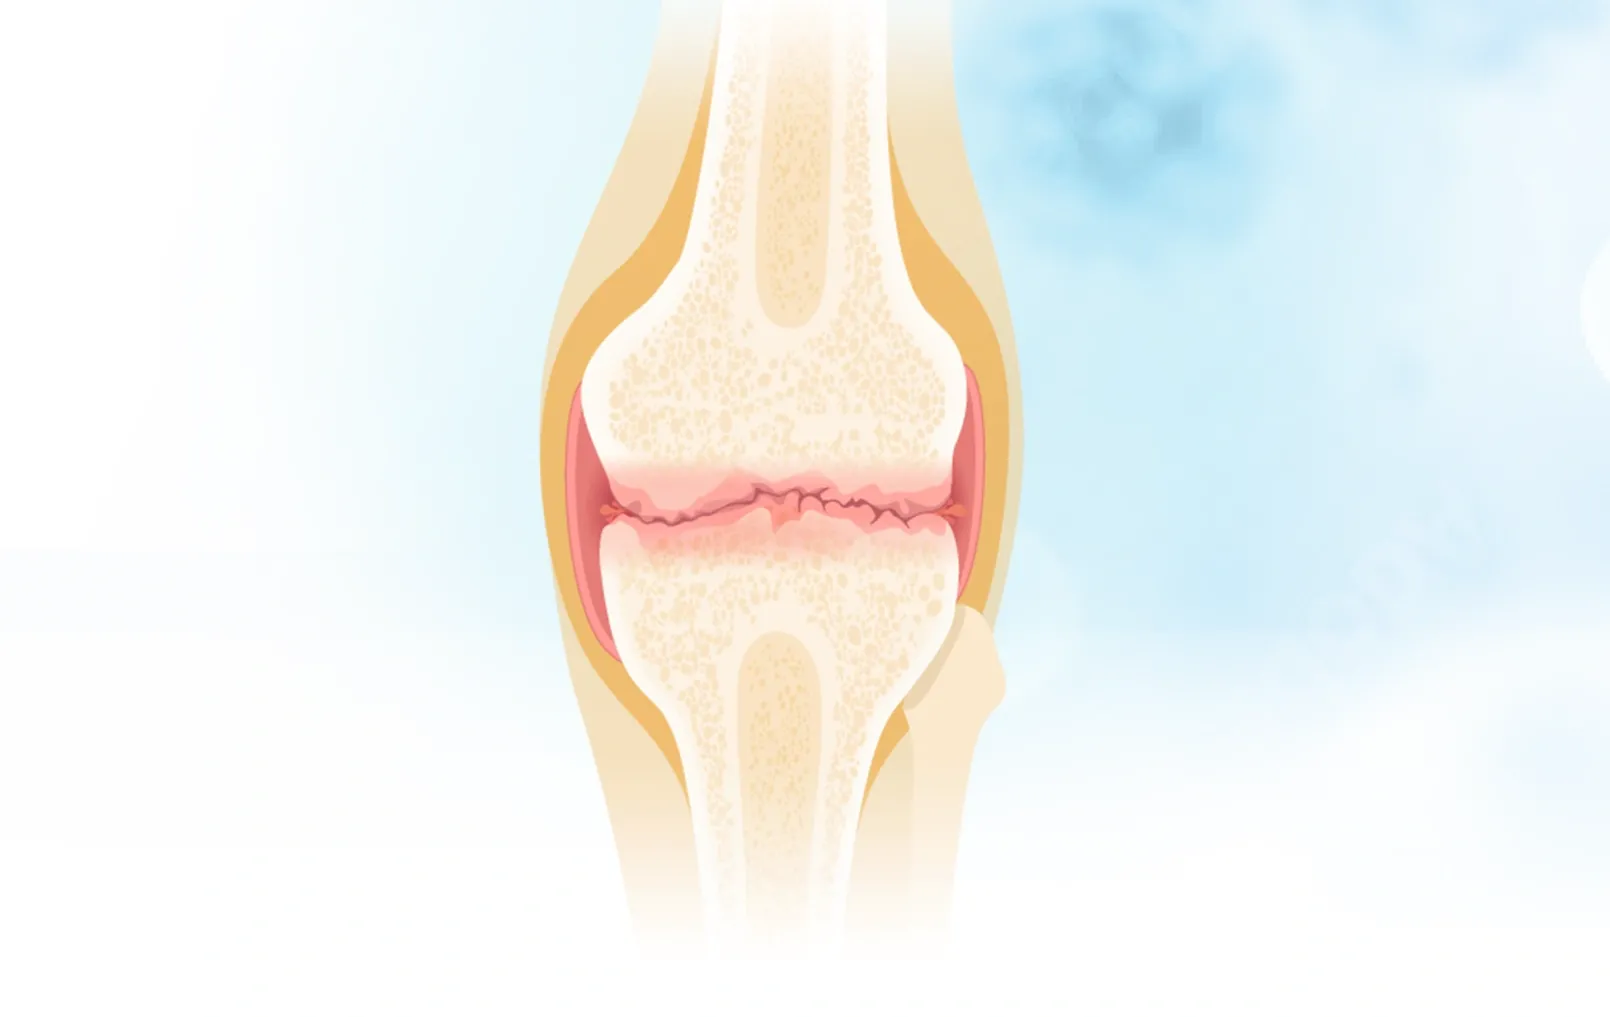

研究人員指出,這項研究的特別之處在於它首次探討飲食與大腿脂肪的關係,而過去研究則表明,大腿肌肉質量和功能下降可能與膝關節炎有關,因此對於患有膝關節或髖關節炎風險而尚未發病的成年人來說,盡量避免進食攝取超加工食物可能有助預防病情惡化。他們強調,關節炎與肥胖和不健康的生活模式息息相關,改變生活方式是控制和治療病患的重要一環。

大腿肌肉質量和功能下降可能與膝關節炎有關。